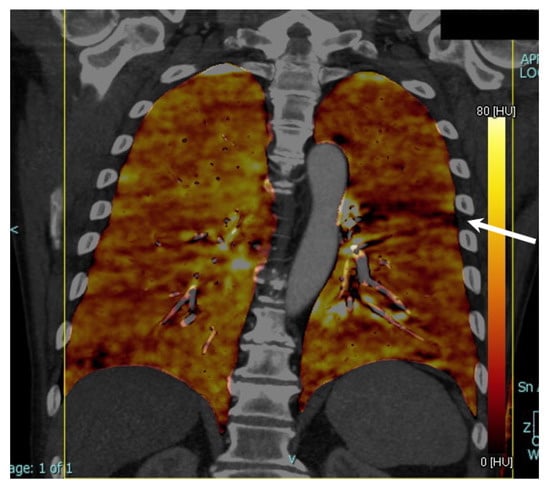

Quantitative Assessment of Lung Volumes and Enhancement in Patients with COVID-19: Role of Dual-Energy CT

2.3. Imaging Post-Processing

3. Results